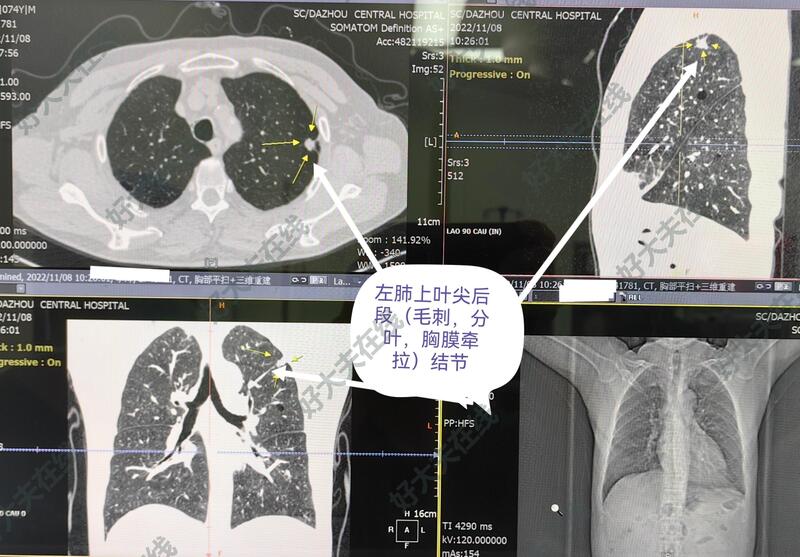

图1-5,女性,45岁,体检发现右肺上叶前段结节,亚实性(磨玻璃)结节、毛刺、分叶、胸膜牵拉等,短期随访结节不消散。胸腔镜微创手术切除,病理报告为肺浸润性腺癌。

图6-10,男性,74岁,体检发现左肺上叶尖后段结节,亚实性磨玻璃样,毛刺、分叶、胸膜牵拉等,也短期随访,结节不改变,自身和子女的心里压力大(一月内反复不同医院做CT等)。胸腔镜微创手术切除,术中:整个胸膜腔完全闭锁粘连,彻底游离粘连,予以左上肺结节切除,病理报告为良性病变。